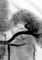

Грудная аортография ( ангиография грудной аорты и ее ветвей) показана для распознавания аневризмы грудной аорты (рис. 2), коарктации аорты и других аномалий ее развития, а также недостаточности клапана аорты.

Различают непрямую и прямую грудную аортографию. При непрямом методе рентгеноконтрастный катетер вводят через локтевую или бедренную вены в правое предсердие, правый желудочек или в легочную артерию. Прямую грудную аортографию проводят путем катетеризации бедренной или подключичной артерии.